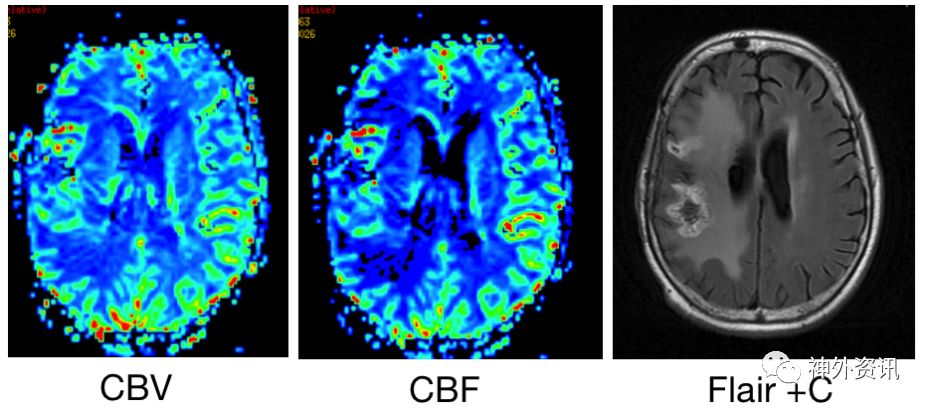

患者10天前无明显诱因出现自觉左侧头面部及肢体发热,伴左上肢肢体乏力及口齿不清,至我院就诊。头部增强MRI示:右侧额叶占位性病变,T1低信号,T2高信号,强化后呈不均匀强化(图1)。以“颅内占位性病变”收住入院。

图1.头部MRI增强右侧额叶可见一片状不规则肿块; T1WI上为稍低信号,T2WI上为略高但混杂信号,有不均匀明显强化,约2.8cm×4.3cm×1.9cm。伴有周围水肿。有轻度占位效应。灌注成像:强化肿块区CBF、CBV增高。磁共振波谱:额病灶及周围NAA峰下降,Cho峰升高,伴有脂质乳酸峰出现,提示肿瘤性病变。

术后9.6个月加做灌注成像和Flair增强(图6)

图6. 术后9.6个月的磁共振灌注影像和Flair增强,显示增强病灶具有升高的血流量和血容量,Flair增强较T1增强略弱。

鉴于肿瘤血流速度和血容量高于正常,Flair序列增强强度低于T1增强。诊断考虑肿瘤复发。

鉴别间变假性进展与肿瘤复发的单次检查目前首选磁共振灌注成像[4]。但是并非所有医院都有条件做磁共振灌注检查。我们推荐做“液体衰减反转恢复(flair)”序列的增强检测,是一种简便易行的检查。通常肿瘤复发病灶的flair增强低于或等于T1增强的信号,而假性进展病灶的flair增强后信号通常超过T1增强序列[5]。(图7)